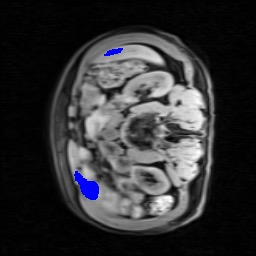

Transformers have made remarkable progress towards modeling long-range dependencies within the medical image analysis domain. However, current transformer-based models suffer from several disadvantages: (1) existing methods fail to capture the important features of the images due to the naive tokenization scheme; (2) the models suffer from information loss because they only consider single-scale feature representations; and (3) the segmentation label maps generated by the models are not accurate enough without considering rich semantic contexts and anatomical textures. In this work, we present CASTformer, a novel type of generative adversarial transformers, for 2D medical image segmentation. First, we take advantage of the pyramid structure to construct multi-scale representations and handle multi-scale variations. We then design a novel class-aware transformer module to better learn the discriminative regions of objects with semantic structures. Lastly, we utilize an adversarial training strategy that boosts segmentation accuracy and correspondingly allows a transformer-based discriminator to capture high-level semantically correlated contents and low-level anatomical features. Our experiments demonstrate that CASTformer dramatically outperforms previous state-of-the-art transformer-based approaches on three benchmarks, obtaining 2.54%-5.88% absolute improvements in Dice over previous models. Further qualitative experiments provide a more detailed picture of the model's inner workings, shed light on the challenges in improved transparency, and demonstrate that transfer learning can greatly improve performance and reduce the size of medical image datasets in training, making CASTformer a strong starting point for downstream medical image analysis tasks.